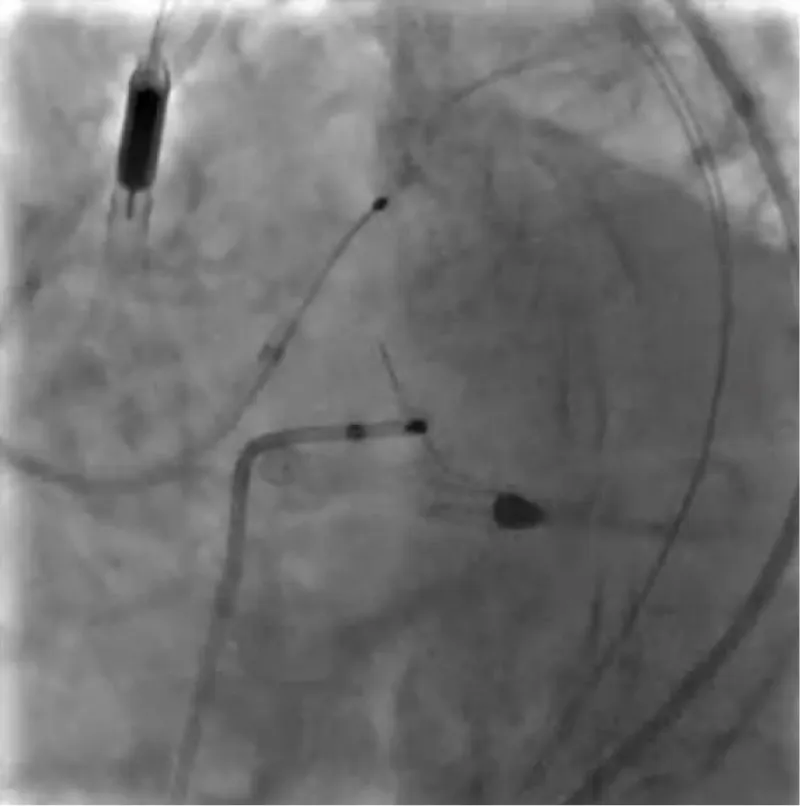

The clinical case concerns an 81-year-old woman with a history of systemic arterial hypertension, hypercholesterolemia, paroxysmal atrial fibrillation, chronic kidney disease, iron-deficiency anemia, and bilateral carotid atheromatosis for which she underwent a Carotid Endarterectomy (CEA) procedure. Additionally, she had a history of breast carcinoma, treated with surgery, subsequent chemotherapy, and ongoing Letrozole therapy. In 2019, the patient presented to the emergency department due to exertional dyspnea and low-threshold angina. During hospitalization, high average ventricular response (109 BPM) atrial fibrillation was diagnosed. Routine lab tests showed rising of hsTN-I (peak 800 pg/dL) and pro-BNP (peak 2476 pg/mL) and anemia Hb 9.1 g/dL. Echocardiography revealed severe depression of the left ventricular function (ejection fraction of 30%, with antero-apical akinesia) and low-flow-low-gradient aortic stenosis (mean gradient of 26 mmHg and AVAi of 0.5 cmq/m2 and SVi 29 mL/m2). So it was performed a Dobutamine stress Echo showed a rise of SVi up to 38 mL/m2 and a mean aortic gradient of up to 48 mmHg. Coronary angiography showed the right dominant coronary artery, of good caliber and course, with no angiographically significant lesions (Figure 1). The Left Main artery, with good caliber, had a 90% calcific stenosis at the distal segment, involving the proximal segment of the Left Anterior Descending artery. The Left Circumflex artery, with good caliber and course, presented a 30% ostial stenosis. The Intermediate Branch, with good caliber and course, showed 80% stenosis at the proximal segment (Figure 2). The Left Anterior Descending artery, also of good caliber and course, was diffusely atherosclerotic with a long, severely calcific 80% stenosis at the mid-distal segment (Figure 3). Therefore, the case was discussed by a multidisciplinary Heart team at our center. The STS score calculated indicated a mortality risk of 11.4%. Due to this high risk, surgical treatment was not considered, and the patient underwent a four-step percutaneous intervention. Before the intervention, a CT angiography was performed, revealing an aortic annulus area of 433.2 mm2, a perimeter of 75.3 mm, and a coronary height from the annulus of 10 mm. The right common femoral artery mean diameter was 6.1 mm2 and the external iliac artery was 8.4 mm2 with moderate tortuosity without significant calcification (Figure 4-6). Therefore, a 23 mm Edwards Sapien 3 valve was chosen. Our strategy consisted of 4 steps:

Figure 2: The Left Main artery, with good caliber, had a 90% calcific stenosis at the distal segment, involving the proximal segment of the Left Anterior Descending artery. The Left Circumflex artery, with good caliber and course, presented a 30% ostial stenosis. The Intermediate Branch, with good caliber and course, showed 80% stenosis at the proximal segment.